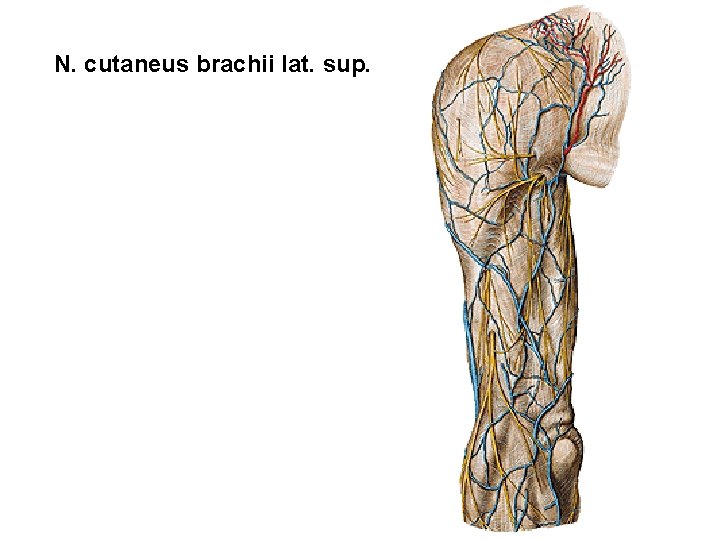

N. cutaneus brachii lat. sup.

N. cutaneus brachii lat. sup. N. cutaneus brachii lat. inf. N. cutaneus antebrachii lat. N. medianus N. ulnaris N. cutaneus brachii med. N. cutaneus antebrachii med. R. spf. n. rad. N. cutaneus brachii post. N. cutaneus antebrachii post. R. palmaris n. ulnaris